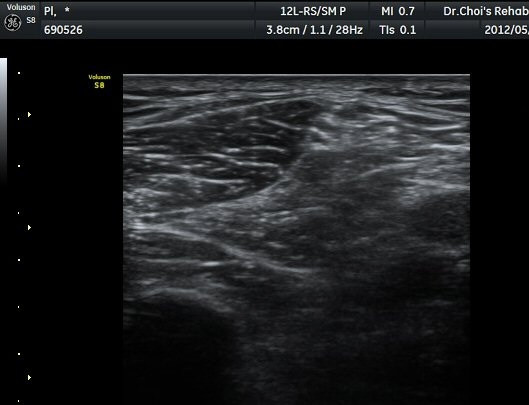

ŽÃËÀÚ¸¦ Á¶±Ý ´õ ¾Æ·¡·Î À̵¿ÇÏ´Ï ºñ°ñÀÇ ¾ÕÂÊ¿¡¼­ ÃѺñ°ñ½Å°æ õºñ°ñ½Å°æ°ú ½Éºñ°ñ½Å°æÀ¸·Î ³ª´©¾îÁø´Ù(±×¸² 6).